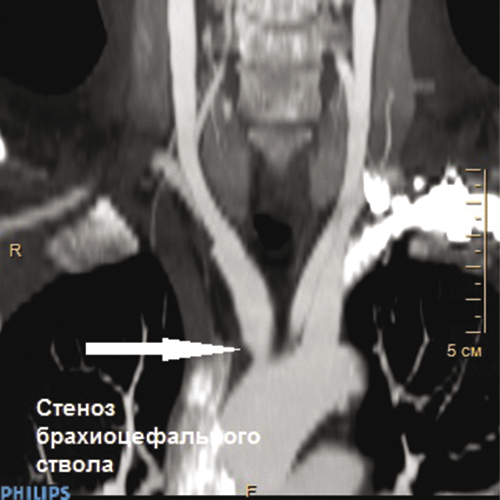

Пациент К., 55 лет, поступил в отделение сосудистой хирургии ФГБУ ФНКЦ ФМБА России 30.08.2017 г. с жалобами на частые головные боли, выраженные головокружения и пошатывания при ходьбе, которые беспокоят в течение 2 лет. Эпизодов острого нарушения мозгового кровообращения (ОНМК) не было. В анамнезе АББШ, неоднократные тромбэктомии и реконструкции дистальных анастомозов с обеих сторон. При физикальном осмотре отсутствует пульсация на ППА, градиент артериального давления на верхней конечности 40 мм рт. ст. При дуплексном сканировании выявлены окклюзия ППА в первом сегменте с ретроградным кровотоком по позвоночной артерии, коллатеральный кровоток по правой плечевой артерии. При КТ с контрастным усилением визуализированы критический стеноз БЦС, окклюзия ППА в первом сегменте без значимых изменений позвоночных и сонных артерий в экстра- и интракраниальных отделах (рис. 1, 2). В связи с наличием клинических проявлений сосудисто-мозговой недостаточности (СМН) на фоне выявленной патологии БЦА были определены показания к оперативному лечению в целях профилактики ОНМК.

Рис. 1. КТ с контрастным усилением: критический стеноз брахиоцефального ствола

Рис. 2. КТ с контрастным усилением: окклюзия правой подключичной артерии в первом сегменте